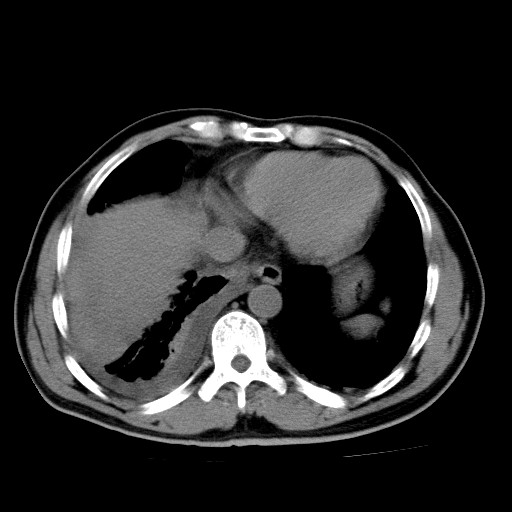

男,54岁,咳嗽,右侧胸痛10天。肺窗>150k,传不了

右肺中心型肺癌并右下肺不张,右侧胸膜纵隔转移。

右中央型肺癌并右肺下叶不张,纵隔内及右胸膜转移,右胸腔积液

考虑   右肺癌伴右下肺部分不张,阻塞性肺炎,纵隔淋巴结增大,右侧胸腔积液其他待排

考虑右肺下叶中央型肺癌并右肺下叶不张,纵隔淋巴结内及右胸膜转移。建议增强。

右下叶大片实变,肺门未见明显肿块影。有胸腔积液和纵隔内肿大淋巴结影。没有增强和肺窗,不好定。

考虑:1、右下叶周围型肺癌伴胸膜、纵隔淋巴转移?

右下叶大片性阻塞性肺炎,肺门未见明显肿块影,纵隔内可见肿大淋巴结影,右见右侧胸腔积液及右侧胸膜增厚。

考虑:右侧中心性肺癌?伴纵隔淋巴结转移。建议上传肺窗。